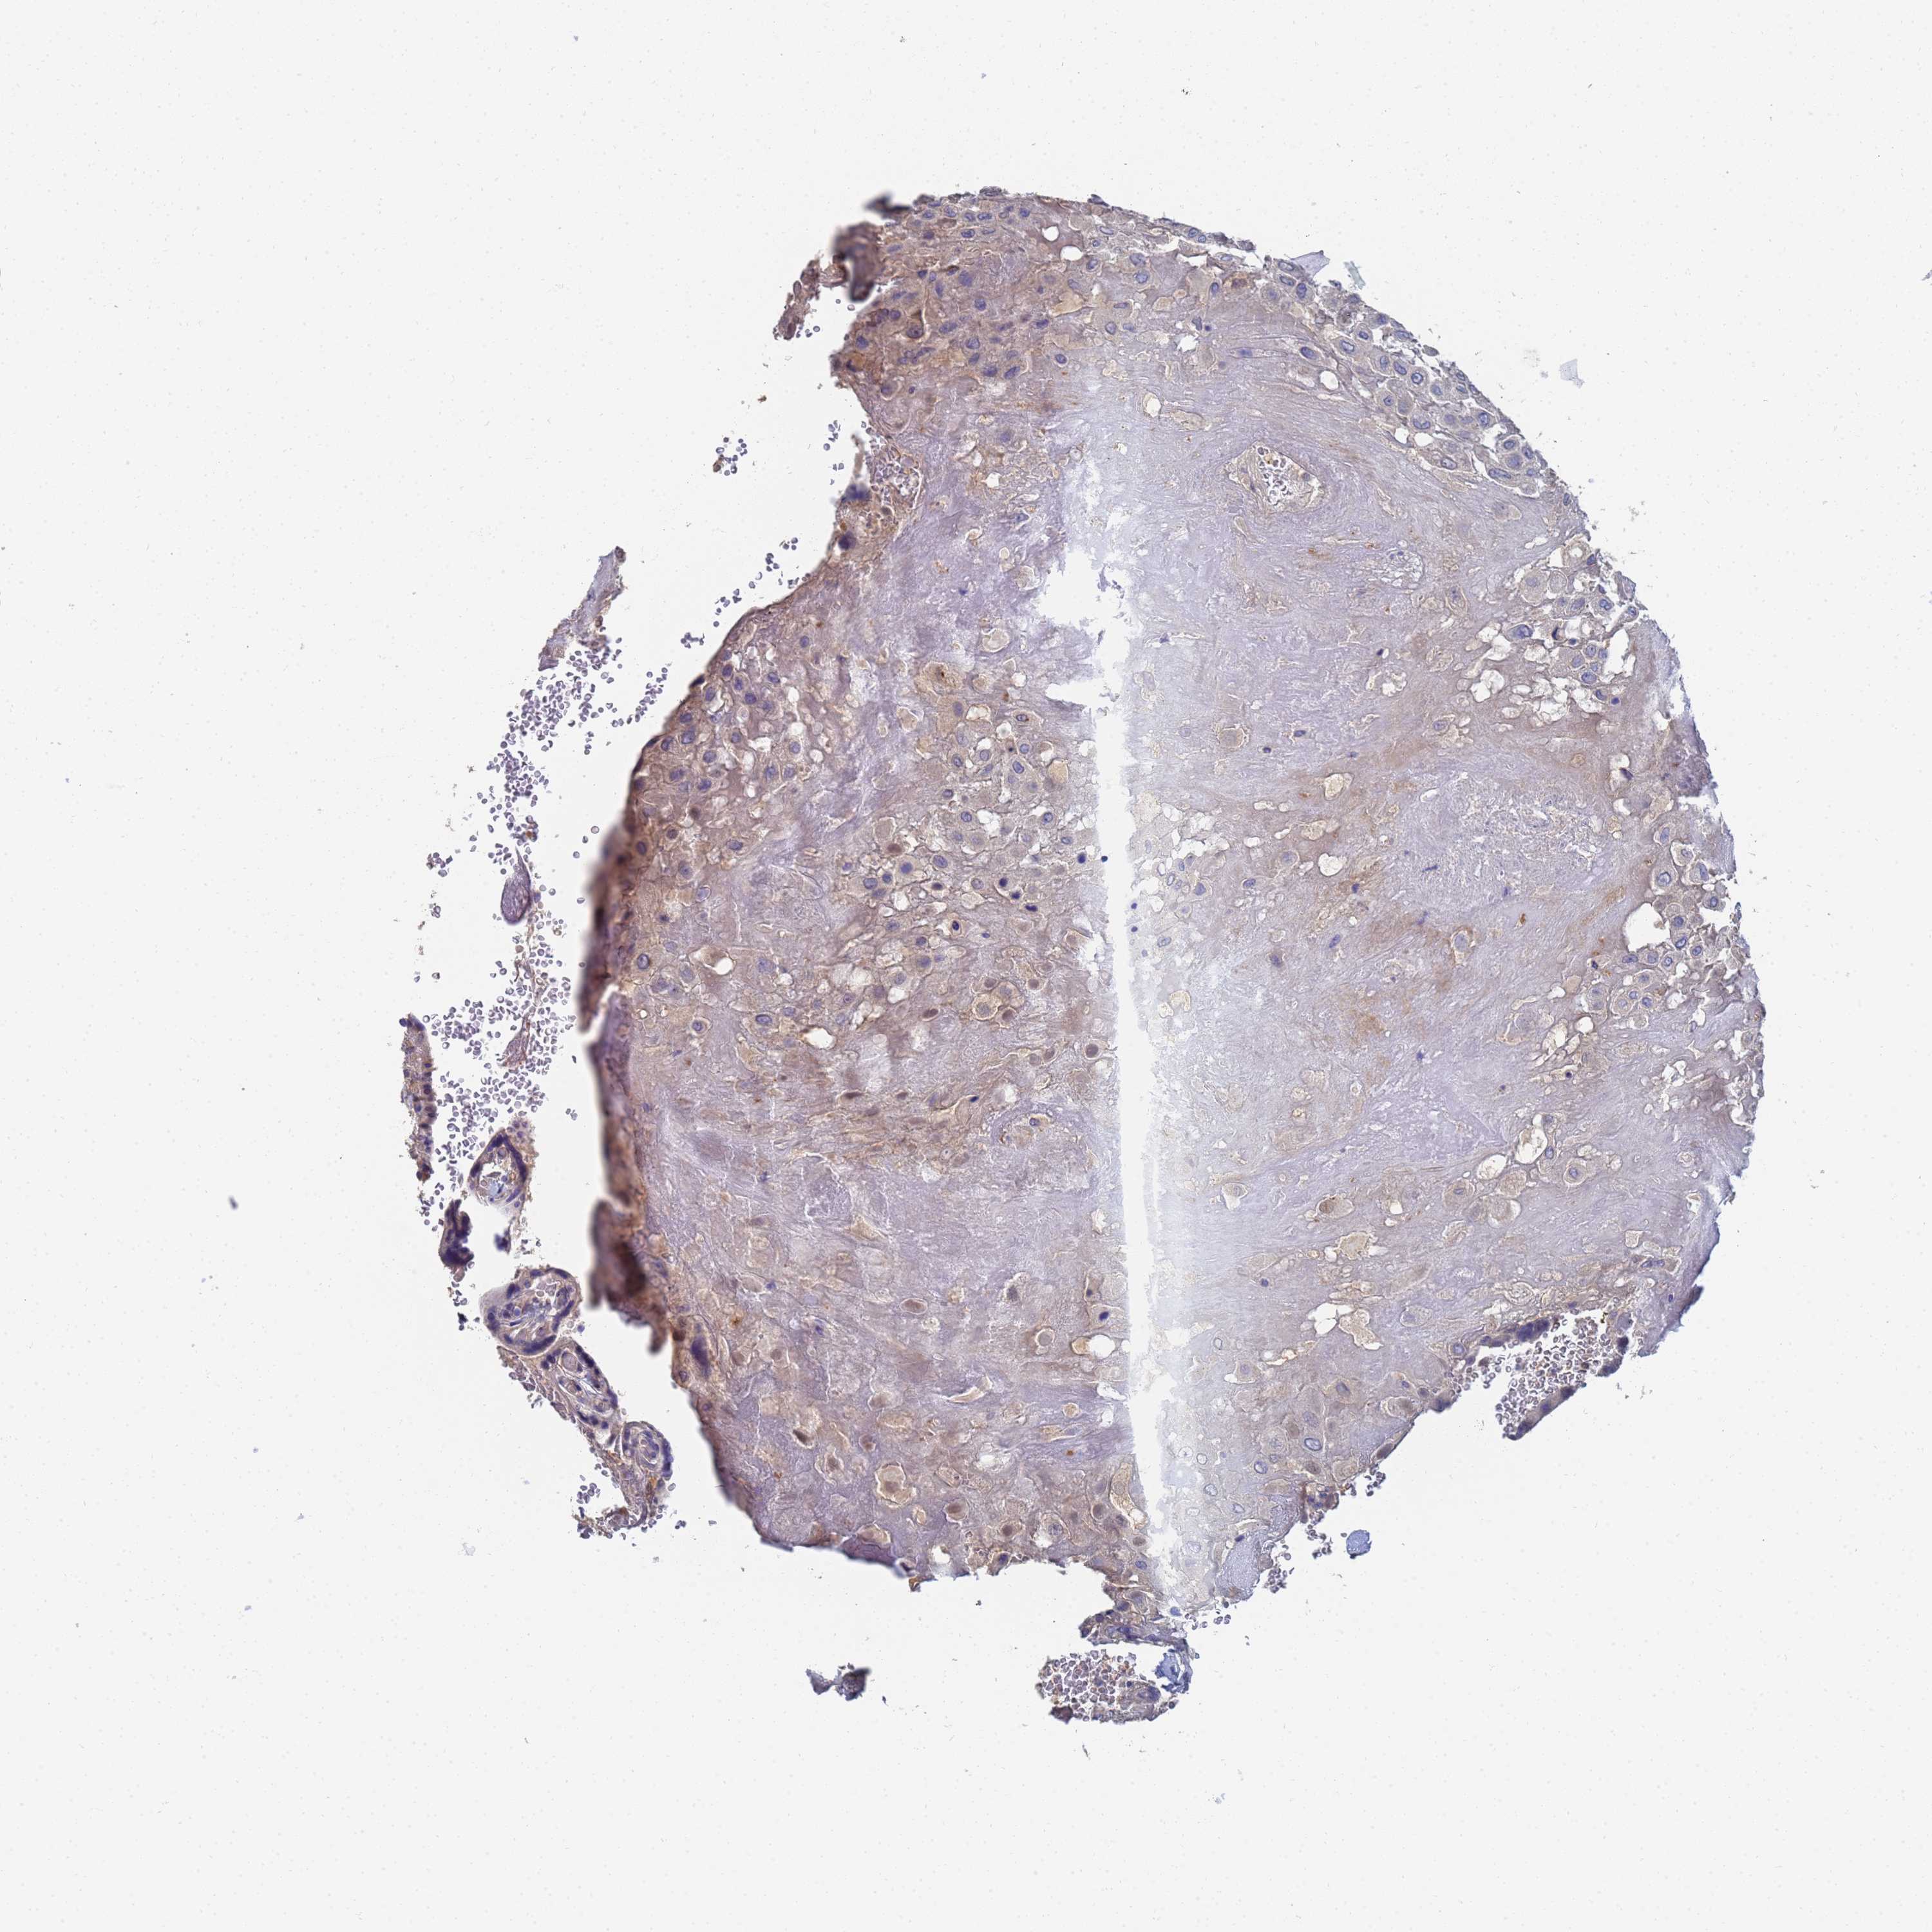

LBX2